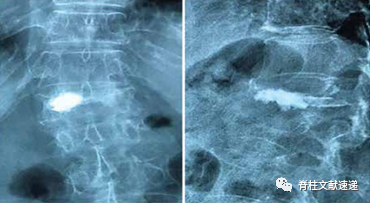

图注:图A显示PKP术后水泥分布良好;图B显示PKP术后骨水泥分布分离;

图注:PVP术后X线结果显示骨水泥分布较为满意;

图注:PVP术后X线结果显示骨水泥分布较差;